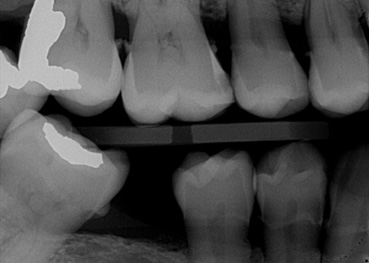

- Figure 3a. Radiographic image

- Figure 3b. Same image with annotations

Source: Overjet, Inc

AI-enabled programs that assist clinicians have existed for some time, such as evaluating the presence and stage of caries lesions based on computerized analysis of radiographs, assisted periodontal charting based on digital data transmission during a periodontal examination, and patient risk assessment programs. Commercially available AI offers more complex assistance with evaluations and diagnoses. Several start-up companies offer AI systems that can assess multiple types of radiographs to identify teeth, restorations, endodontically-treated teeth, implants, and can identify and evaluate dental caries, calculus, periodontal disease, periapical lesions, other pathologies, and anatomical anomalies. (Figure 3a,b) Results from a number of AI systems are supportive of its use in evaluating bitewing, periapical and panoramic radiographs, and in assessing dental caries, and bone loss quantification.16Schwendicke F, Rossi JG, Göstemeyer G et al. Cost-effectiveness of Artificial Intelligence for Proximal Caries Detection. J Dent Res 2021;100(4):369-76. doi: 10.1177/0022034520972335. ,17Baydar O, Różyło-Kalinowska I, Futyma-Gąbka K, Sağlam H. The U-Net Approaches to Evaluation of Dental Bite-Wing Radiographs: An Artificial Intelligence Study. Diagnostics (Basel) 2023;13(3):453. doi: 10.3390/diagnostics13030453.,18Başaran M, Çelik Ö, Bayrakdar IS et al. Diagnostic charting of panoramic radiography using deep-learning artificial intelligence system. Oral Radiol 2022;38(3):363-9. doi: 10.1007/s11282-021-00572-0.,19Overjet. https://www.overjet.ai/dso/ In a recent study, the ability of a single AI system to detect dental caries as well as periapical periodontitis was found to be more accurate than clinical detection alone among young dentists.20Li S, Liu J, Zhou Z et al. Artificial intelligence for caries and periapical periodontitis detection. J Dent 2022;122:104107. doi: 10.1016/j.jdent.2022.104107. Additionally, the overall accuracy for experts increased with the aid of the AI system and reduced inter-observer differences.